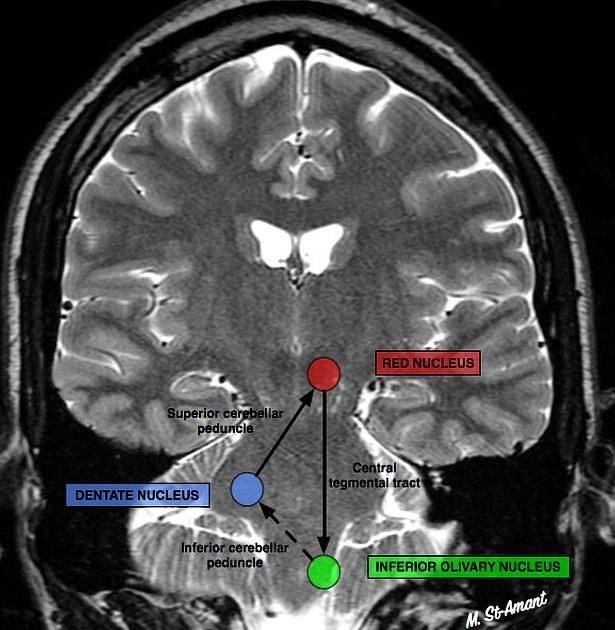

Сегментарный миоклонус: эссенциальный и симптоматический миоклонус неба, иногда рассматривающийся как тремор. Эссенциальный обусловлен дисфункцией, а симптоматический — структурным поражением области треугольника Молляре (в проекции которого локализуются связи между зубчатым ядром мозжечка, красным ядром и нижним оливарным ядром) (рис. 7) [36].